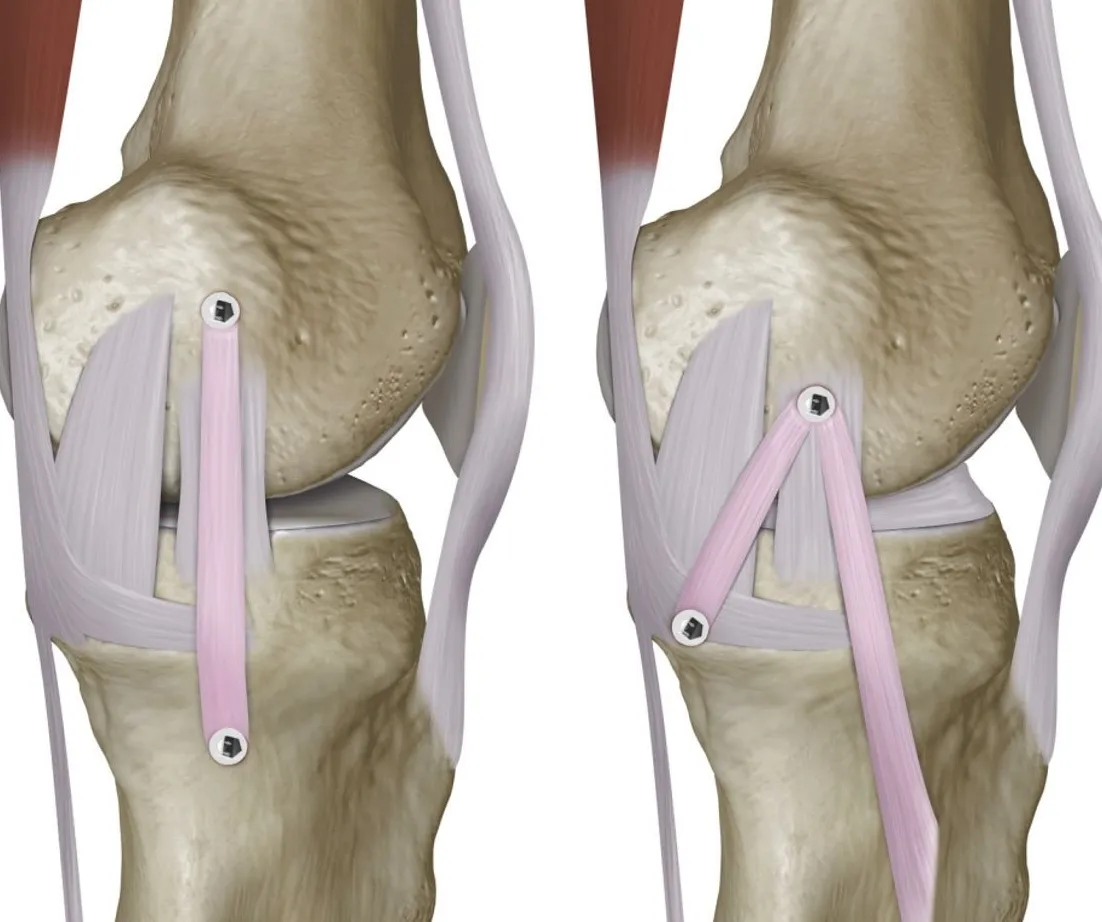

La tendinitis del ligamento colateral medial es una inflamación o irritación del ligamento colateral medial (LCM).

Este ligamento se encuentra en la parte interna de la rodilla y cumple una función muy importante: estabilizarla y evitar que se desplace lateralmente.

- Pruebas de imagen: En algunos casos, se pueden utilizar radiografías, resonancias magnéticas o ecografías para identificar la inflamación específica del LCM.